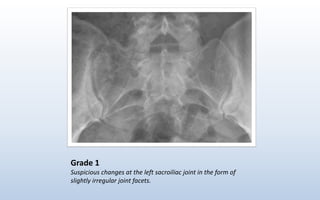

Grade 1

Suspicious changes at the left sacroiliac joint in the form of

slightly irregular joint facets.